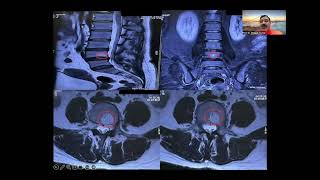

What is Slip Disc/Scatica? 70–96% can be cured without surgery, complete information, in simple a...